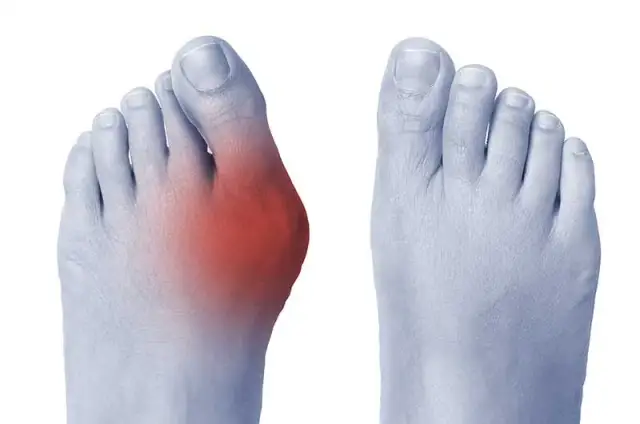

Masz haluksy? Odkryj skuteczne domowe sposoby na ból, ćwiczenia, leczenie zachowawcze i dowiedz się, kiedy iść do lekarza.

Co stosować na haluksy? Poznaj kompleksowy przewodnik po domowych sposobach, aparatach, fizjoterapii i operacji. Znajdź ulgę!

Sprawdź nasz przewodnik po haluksach! Dowiedz się, jak zatrzymać postęp, poznać metody leczenia zachowawczego i operacyjnego.